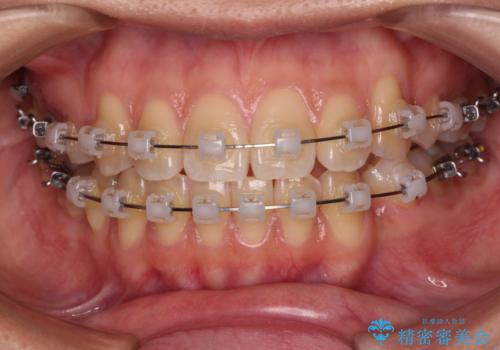

- クリアブラケット

- 2年6ヶ月

- 10-30回